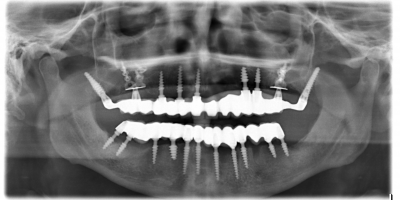

Case I

The patient a lady of 53 had advanced periodontitis which made her came several times to the clinic for emergency treatment of pain. At a point patient wanted a permanent solution to this problem. Surgery was done in one session under local anesthesia, teeth in the maxilla and mandible were extracted and implants were placed.

Three weeks after initial consultation, patient ́s mouth was rehabilitated with definitive metal ceramic bridges. This was made possible due to the achieved bicortical anchorage in the anterior part and a strong cortical anchorage at the pterygoid plates (75 N/cm) in the maxilla, these anchorage ensured high primary stability which encourages immediate loading.

Case II

The patient a lady of 56 attended clinic with periodontal problems. After intra oral examination and radiological reviews, it was observed that the width and height of alveolar bone is not enough for classic implant placement. On the first appointment all teeth in the maxilla were extracted, and implants were placed, under local anesthesia. Pterygoid Implants C 3.5/20 mm were placed in position 18 and 28 to get a high primary stability, same implants were used at the extraction’s sockets and in the rest of the maxilla.

A metal ceramic bridge was fabricated after frame try-in. Three weeks after the beginning of the treatment, the gum has healed nicely, bridge was screw-retained READ MORE